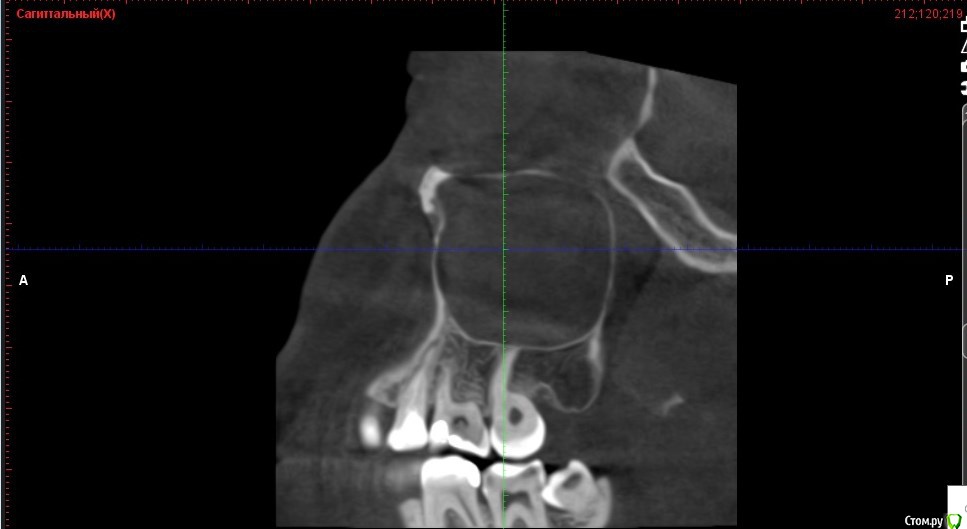

Verasss Опубликовано 28 октября, 2016 Автор Поделиться Опубликовано 28 октября, 2016 Добрый вечер! Ещё раз попытаюсь прикрепить скриншоты КТ от сентября. Если качество совсем не устраивает, подскажите, пожалуйста, какие сделать снимки?К сожалению, программа не позволяет вывести снимки на полный экран и заскриншотить в более хорошем качестве. Ссылка на комментарий

Verasss Опубликовано 28 октября, 2016 Автор Поделиться Опубликовано 28 октября, 2016 еще снимки Ссылка на комментарий

Verasss Опубликовано 28 октября, 2016 Автор Поделиться Опубликовано 28 октября, 2016 и еще Ссылка на комментарий

Verasss Опубликовано 23 ноября, 2016 Автор Поделиться Опубликовано 23 ноября, 2016 Сделала ещё 1 кт, спустя почти 2,5 месяца после первого. Посмотрите, пожалуйста, есть ли изменения? Напомню, что пункцию гайморовой мне сделали. Ссылка на комментарий